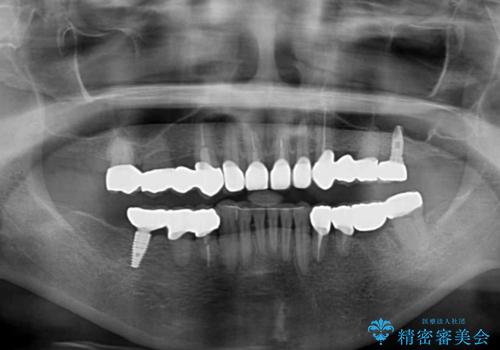

歯肉の状態が落ち着いた後に下顎の矯正治療を行い、その後補綴治療を行うこととしました。

インプラントに対する恐怖心が強く、欠損補綴は極力ブリッジを採用し、インプラントの数は必要最小限としました。

油断をするとすぐに汚れが溜まって歯肉が腫れてきてしまうため、今後も定期的なメインテナンスが重要となります。